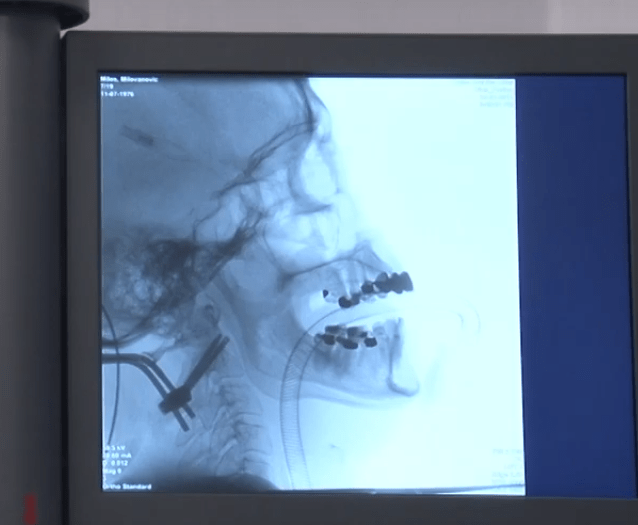

Milovanović Miloš (42 years old) from Ub four months ago had a motorcycle accident during falling off a scooter straight under the car. During accident he got fracture of second cervical vertebra (C2) or axis (dens). Unfortunately, during examination in Hospital in Valjevo fracture was not diagnosed, so his issues with time became worse.

“Intention was to do fixation of the fracture, or to bring together the broken part to the base of the vertebrae. With this, all conditions would be created and in some time would heal as it was before”, says dr Savić.

“During the first operation we have done fixation from occipital bone to second cervical vertebrae. The second one was performed from the anterior part of the neck, with special screws that passed through the base of the vertebrae up to broken part in order to close it to the base and to make contact – bone to bone. That is a guarantee for a definitive fixation of the fracture and complete healing”, says dr Savić and explains that in case that patient had come immediately after the accident, it would have been needed only the anterior operation.